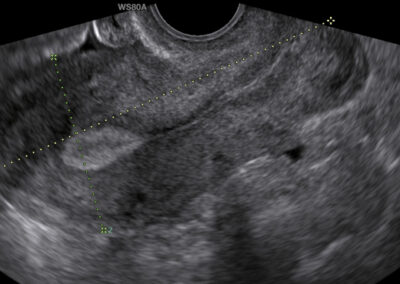

Ultrazvukové vyšetření ženských orgánů

Vyšetříme vnitřní ženské pohlavní orgány (dělohu, vaječníky a vejcovody) a malou pánev. Protože je děloha umístěna v pánvi, provádí se toto vyšetření zpravidla tzv. vaginální sondou přes pochvu. Vyšetření není bolestivé ani nebezpečné a provádí se ideálně při prázdném močovém měchýři.